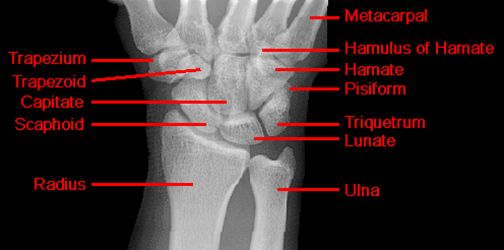

正常腕关节

月骨周围脱位

舟骨骨折

最常见的腕骨骨折

易漏诊

易发生缺血性坏死

儿童少见